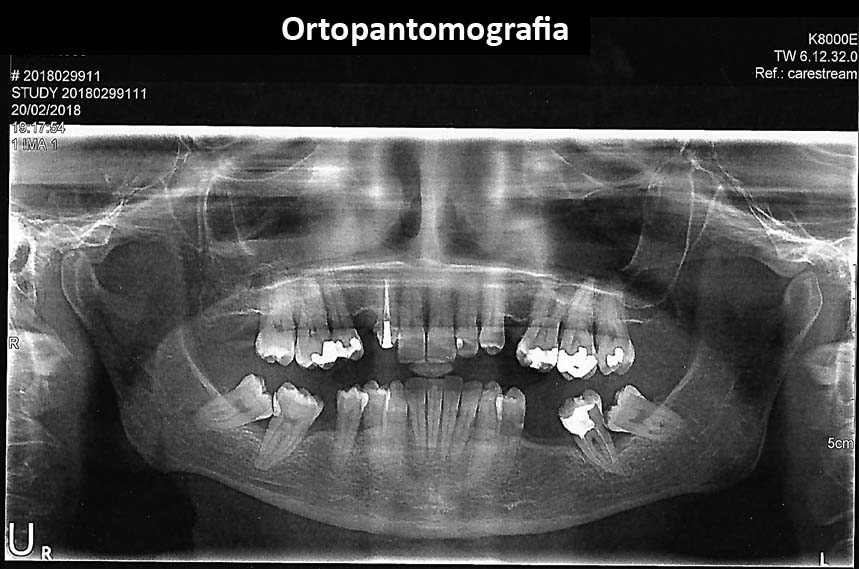

• Radiographies/X´Rays

Urgent treatments are executed if necessary as in the case on the left.